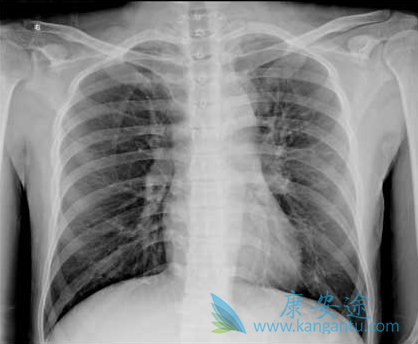

6月16号, 默沙东公司宣布了一项重要的三期临床试验Keynote-024的新进展:在PD-L1高表达的非小细胞肺癌患者中,使用Keytruda的患者在无进展生存期和总生存期方面均比使用化疗的有显著的优势。也就是说:对于PD-L1高表达的晚期肺癌患者,一线治疗使用Keytruda比化疗活得长,活得好。

Keytruda联合化疗用于肺腺癌有效率71%,这是今年ASCO年会刚刚公布的小临床数据,招募未曾化疗的非小肺癌患者,没有EGFR和ALK突变,所以没有使用相应的靶向药治疗。一共招募75名患者,分成三组,分别使用Keytruda联合化疗或者贝伐单抗治疗。C组招募非鳞的非小肺癌患者,接受Keytruda联合卡铂和培美曲塞,24名患者17位肿瘤缩小至少30%,客观有效率71%,无进展生存期10个月。

凭借比较好的二期临床数据,罗氏的PD-L1抗体Tecentriq已经上市。Tecentriq针对晚期肺癌的不少临床数据也已经公布。2015年ASCO公布了罗氏的PD-L1抗体Tecentriq联合化疗的1b临床数据,招募37位患者,接受Tecentriq联合卡铂+紫杉醇或者卡铂 +培美曲塞或者卡铂+蛋白结合型紫杉醇,总的有效率是67%,最重要的是发现有效率和PD-L1表达没有关系。PD-1/PD-L1抗体对晚期肺癌治疗带来新希望。